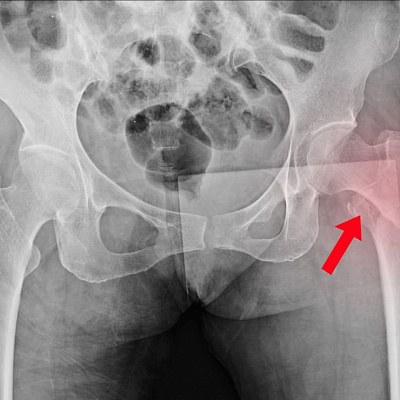

1 стадия — подострая, клинической картины нет. Есть только рентгенографические изменения губчатого вещества костной ткани, а также костного мозга. Нередко патологическое состояние вообще никак не выявляется, остается незамеченным. Но современные методы обследования дают возможность быстро и надежно определить расстройство. Рентген эффективен не всегда.

Для 2 стадии АНГБК характерно существование характерных рентгенографических признаков. Затемнение области костной ткани, микрокровоизлияния и многочисленные патологические переломы, которые хорошо видны по картине лучевой диагностике. Клиническая картина отсутствует или минимальная.

На 3 стадии асептического некроза развиваются характерные анатомические изменения: расширение суставной щели, уплощение костной ткани, укорочение шейки бедра и прочие характерные визуальные признаки. Субъективные ощущения присутствуют. Заболевание сопровождается болью разной степени выраженности. Это разгар патологического процесса.

- рентген (проводится всегда, но на ранних стадиях часто не дает полного представления о характере патологического состояния);

- компьютерная томография, во много раз более точный метод лучевой диагностики, помогает определить заболевание даже на самой ранней стадии, когда симптомов расстройства еще нет;